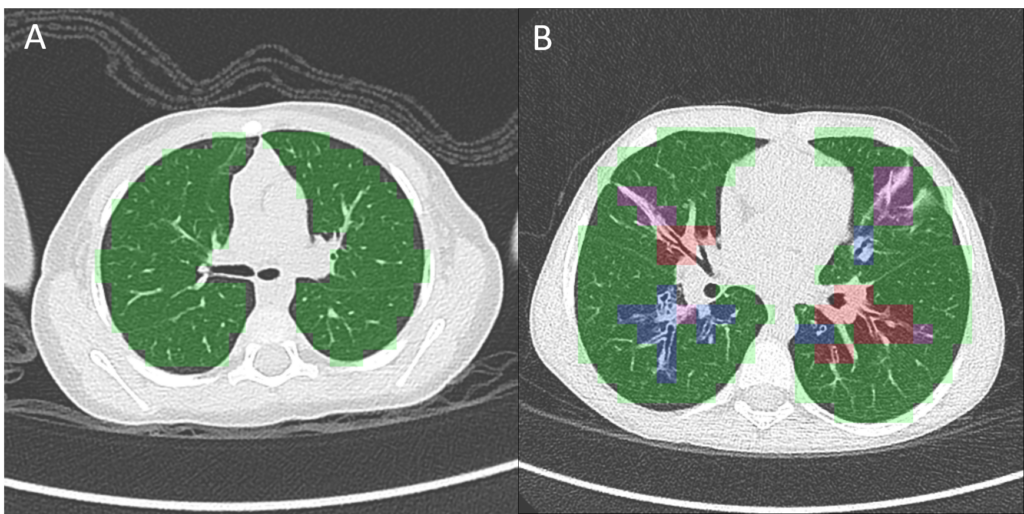

CT scan of (A) a patient with normal lungs and (B) a patient with severe cystic fibrosis, analyzed with PRAGMA-CF. This analysis quantifies disease patterns related to CF, including normal lung tissue (green), bronchiectasis (blue), airway thickening (red) and mucous plugging (pink). Thirona is developing an automated AI solution to quickly and accurately quantify PRAGMA-CF disease patterns.